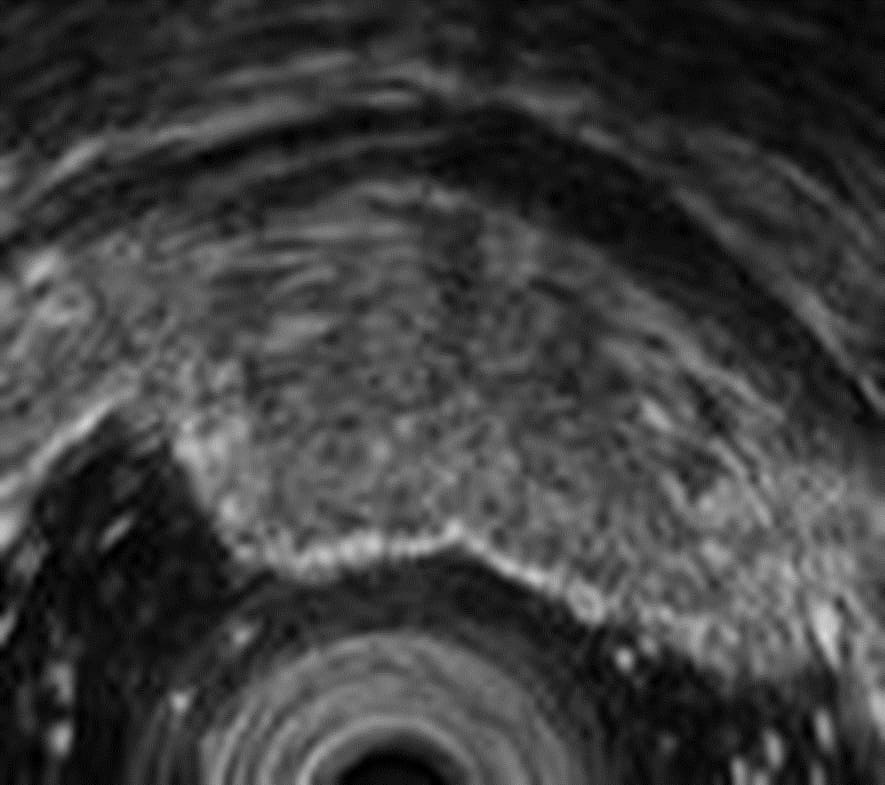

EUS revealed a hypoechoic mass with internal heterogeneity and a heterogeneous shape, mainly situated in the second and third layers of the stomach wall. The tumor boundary was relatively clear, and no infiltration into the fourth layer was observed see in (Figure 3).

Figure 3: Endoscopic ultrasonography. The lesion is present in the second and third layers of the stomach wall. A hypoechoic mass with internal heterogeneity and a heterogeneous shape is observed.

This patient exhibited a curious pathological presentation. In general, hematoxylin and eosin staining of a gastric NET does not show fibrous components. Because a gastric NET consists of a uniform lump of cells, EUS typically shows a uniform hypoechoic mass, similar to a lymph node. However, in this patient, pathological examination of the specimen, removed by ESD, showed a lesion with a fibrous stroma throughout the tumor.

The presence of a fibrous stromal component throughout the tumor may be the reason for the non-uniform hypoechoic overall appearance of the tumor in this patient. In other words, the hypoechoic mass with a non-uniform shape may not only reflect the tumor component but also the fibrosis, which may be different from the usual NET presentation.